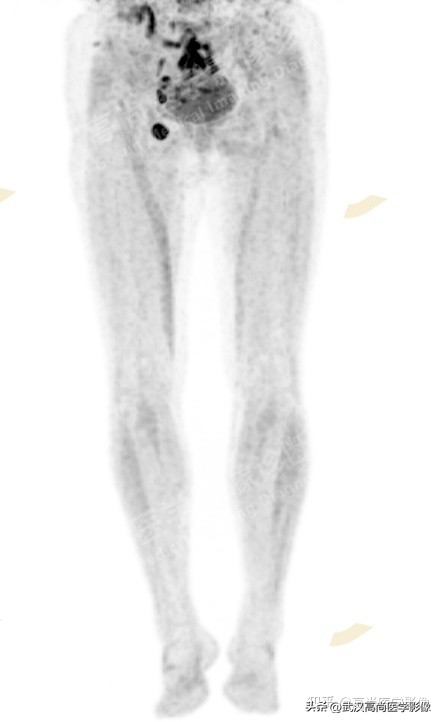

1、 常规全身PET/CT检查范围内未见明显高代谢原发灶,考虑有无可能是下肢皮肤癌转移,故查看询问双下肢是否有黑痣且加扫双下肢,但仍未发现可能的原发病灶。